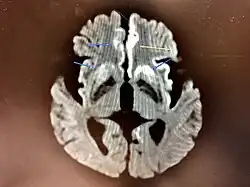

MRI of iCJD because of growth hormone

The defective protein can be transmitted by contaminated harvested human brain products, corneal grafts,[28] dural grafts,[29] or electrode[30] implants and pituitary human growth hormone, which has been replaced by recombinant human growth hormone that poses no such risk.[31]

dwMRI, FDG PET and post mortem histology from a patient who presented with sCJD aged 66

Brain FDG PET-CT tends to be markedly abnormal, and is increasingly used in the investigation of dementias.

• Patients with CJD will normally have hypometabolism on FDG PET.[55]